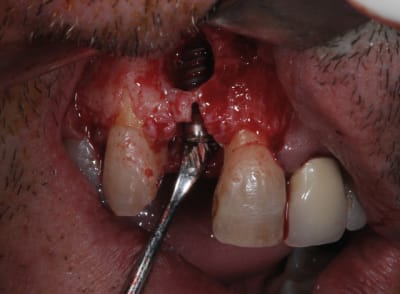

Vous tenteriez l'EII dans ce cas ci

Il y a 3.6 mm d'os au dessus du granulome

si tu veux aller au casse pipe....

pas que pour le granulome...d'ailleurs...mais aussi parce que tu as une belle fracture vestibulaire qui fait que la corticale...bein y en a plus...ou quasi plus...

la seule condition pour tenter: faire une box technique au sonicweld...et encore, autant dans un secteur pas trop esthétique, je dis pas...mais là...si çà foire c'est le drame...